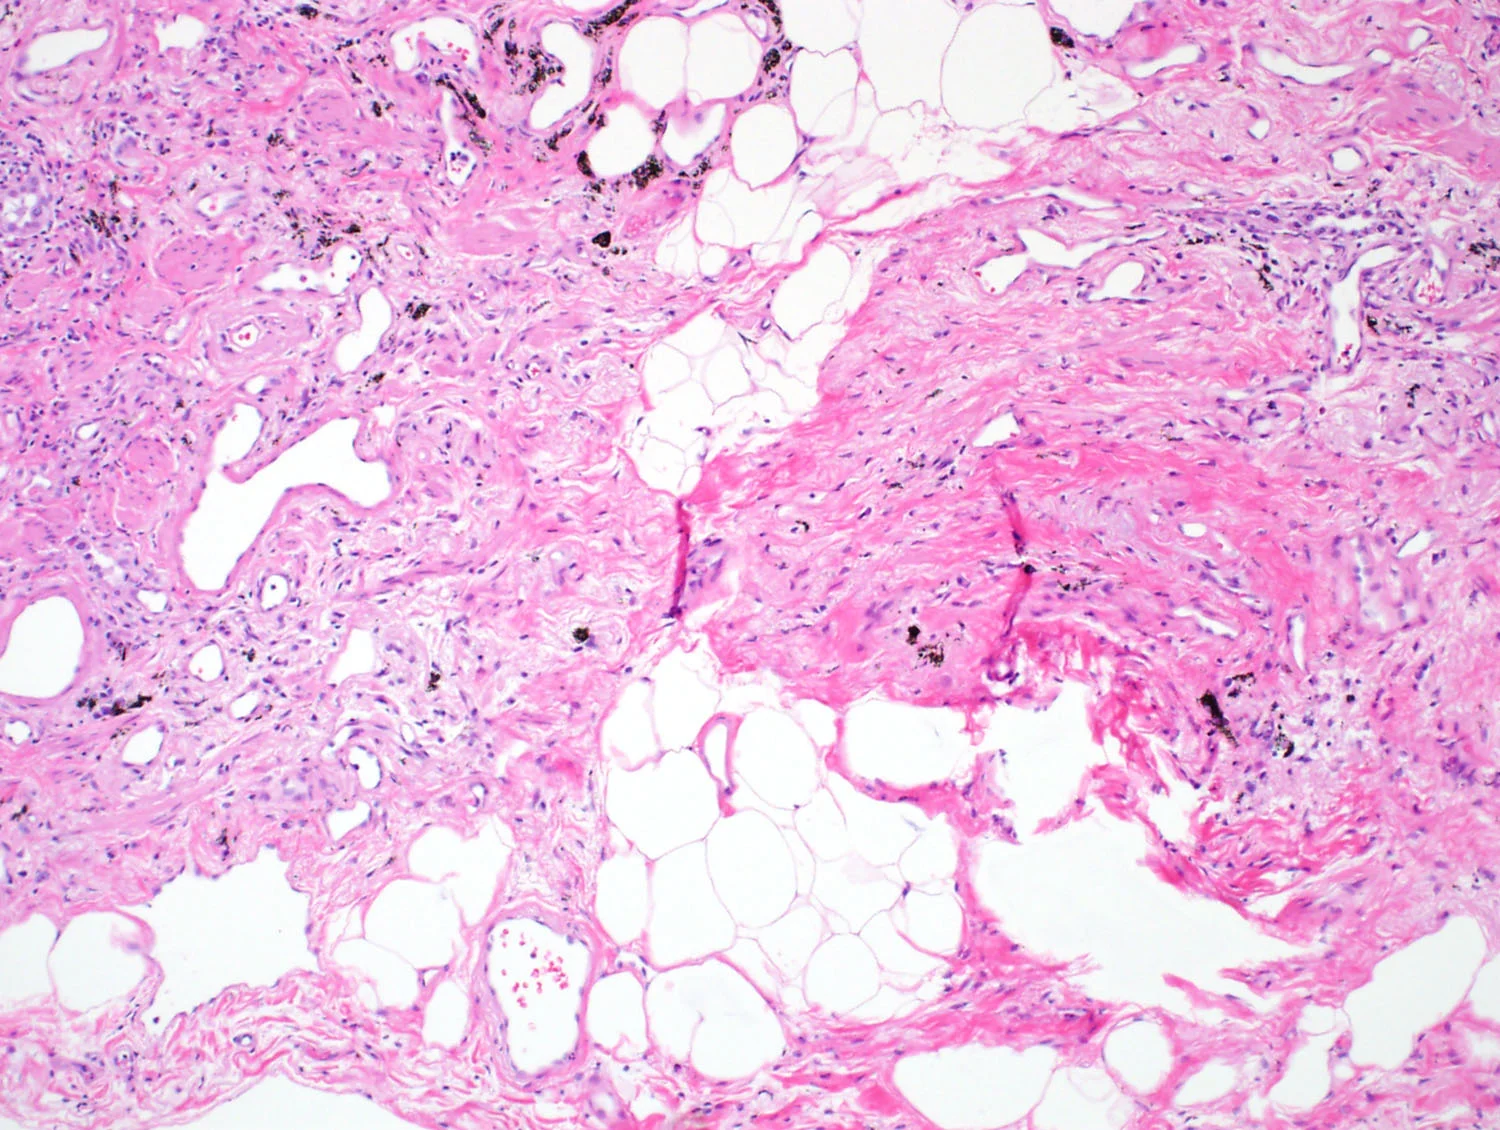

Fatty Metaplasia

Adipoocytes embedded in collagen.